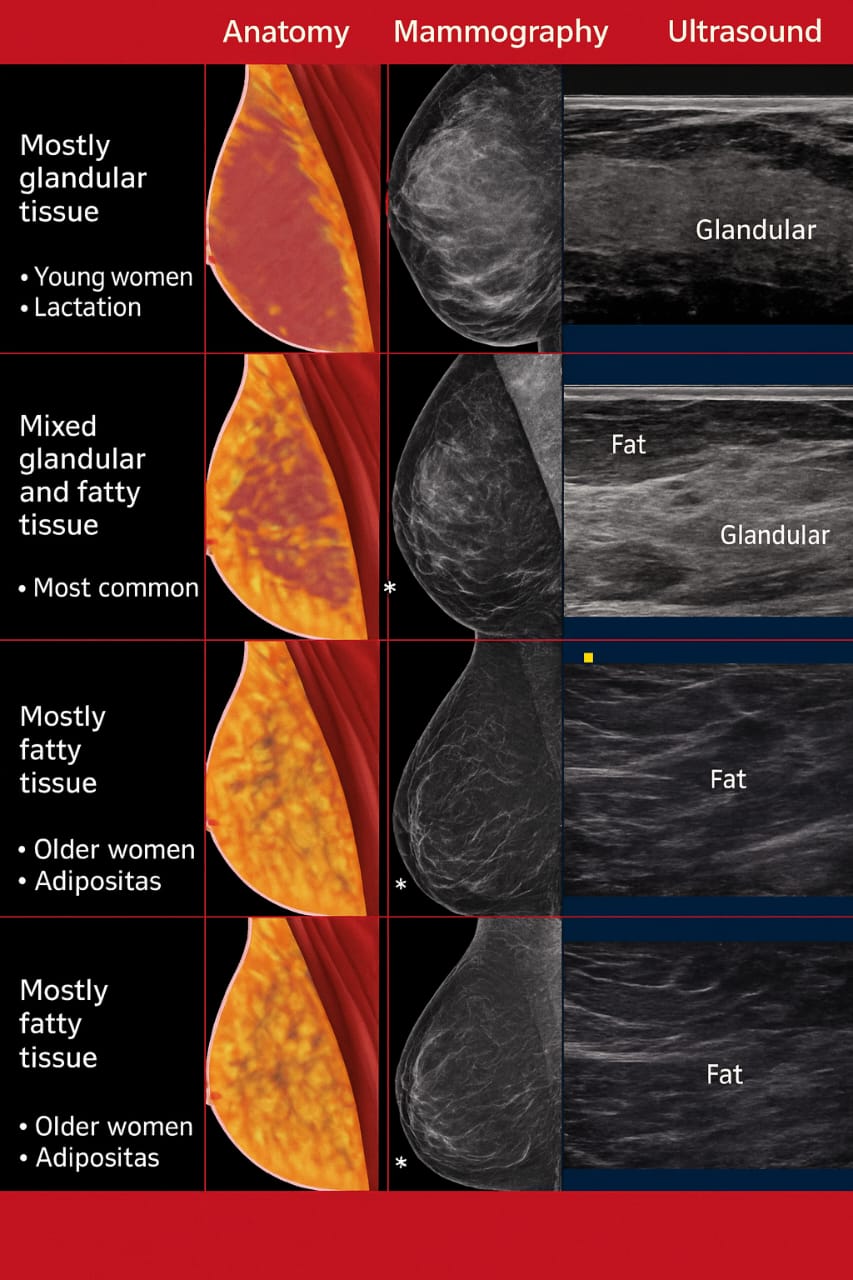

This test allows the radiologist to see inside the breast and determine whether a lump is solid (like a fibroadenoma or tumor) or fluid-filled (like a cyst). It’s especially useful for women with dense breast tissue or for further evaluation after a mammogram or clinical examination.

- Good for women with dense breasts to make sure no small lumps are missed.

- Produces 3D pictures for more detailed checking.

Works well with dense tissue: Can provide a clearer image than a mammogram in dense breasts. Guides biopsies: Helps a doctor accurately take a tissue sample if one is needed.